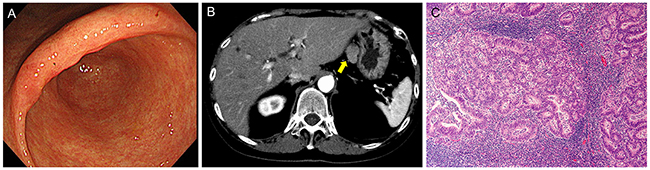

A 68-year-old woman, with a history of eradicated Helicobacter pylori infection, suffered from transient epigastralgia. The patient underwent upper gastrointestinal endoscopy, which elucidated an irregular mucosal lesion in the gastric angle (Figure 1A). A biopsy revealed a tubular adenocarcinoma of the well-differentiated type. Carcinoembryonic antigen (CEA) and carbohydrate antigen 19-9 (CA19-9) levels were 8.5 ng/ml and 50 U/ml, respectively. Although the lesion seemed to be confined within the gastric mucosa and to fulfill the absolute indication of endoscopic resection, a suspicious LN metastatic lesion (23 mm diameter) beside the left gastric artery was noted on a CT scan (Figure 1B). A laparoscopic tumor biopsy revealed that the tumor was an enlarged LN with tubular adenocarcinoma that was histologically similar to the gastric tumor (Figure 1C). Positron emission tomography/CT showed no apparent uptake except in the LN tumor. Thus, the patient was diagnosed to have an early gastric cancer with a regional LN metastasis and underwent the standard distal gastrectomy with D2 lymph node dissection. After surgery, CEA and CA19-9 levels normalized. The patient underwent no adjuvant chemotherapy and has remained in good health without any signs of recurrence or other malignant tumors for 39 months (most recent follow-up).

Figure 1: Preoperative findings. (A) Endoscopy showed irregular mucosa in the lesser curvature of the gastric angle with ill-defined margins from surrounding atrophic mucosa. (B) Computed tomography showed an irregular oval tumor of 23 mm diameter beside the left gastric artery (arrow). (C) Laparoscopic biopsy of the intra-abdominal tumor revealed a metastatic tubular adenocarcinoma in the lymph node. Hematoxylin and eosin (H&E) staining, original magnification, ×100.